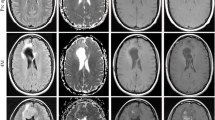

We created discriminative models of different regions of interest (ROIs) using radiomic texture features of neurite orientation dispersion and density imaging (NODDI) and evaluated the feasibility of each model in differentiating glioblastoma multiforme (GBM) from solitary brain metastasis (SBM).

We conducted a retrospective study of 204 patients with GBM (n = 146) or SBM (n = 58). Radiomic texture features were extracted from five ROIs based on three metric maps (intracellular volume fraction, orientation dispersion index, and isotropic volume fraction of NODDI), including necrosis, solid tumors, peritumoral edema, tumor bulk volume (TBV), and abnormal bulk volume. Four feature selection methods and eight classifiers were used for the radiomic texture feature selection and model construction. Receiver operating characteristic (ROC) curve analysis was used to evaluate the diagnostic performance of the models. Routine magnetic resonance imaging (MRI) radiomic texture feature models generated in the same manner were used for the horizontal comparison.

NODDI-radiomic texture analysis based on TBV subregions exhibited the highest accuracy (although nonsignificant) in differentiating GBM from SBM, with area under the ROC curve (AUC) values of 0.918 and 0.882 in the training and test datasets, respectively, compared to necrosis (AUCtraining:0.845, AUCtest:0.714), solid tumor (AUCtraining:0.852, AUCtest:0.821), peritumoral edema (AUCtraining:0.817, AUCtest:0.762), and ABV (AUCtraining:0.834, AUCtest:0.779). The performance of the five ROI radiomic texture models in routine MRI was inferior to that of the NODDI-radiomic texture model.

Preoperative NODDI-radiomic texture analysis based on TBV subregions shows great potential for distinguishing GBM from SBM.